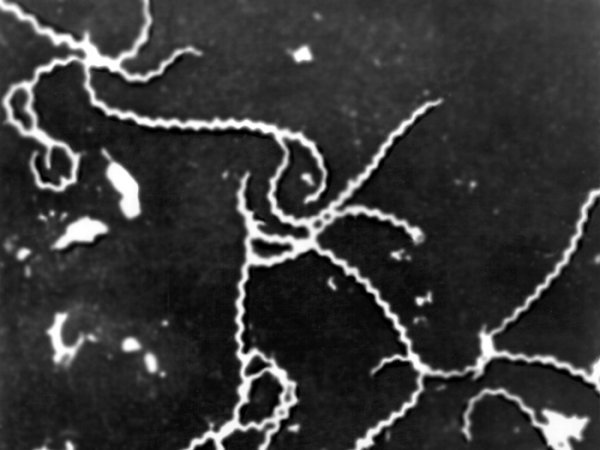

Лептоспіроз – гостра інфекційна хвороба з групи зоонозів (узагальнена назва природно-вогнищевих інфекцій, тобто таких інфекційних захворювань що передаються від тварин до людини). Резервуаром збудника лептоспірозу є дикі гризуни (щури, миші), свійські (свині, велика рогата худоба, собаки) і промислові (лисиці, песці) тварини, які виділяють лептоспір у довкілля з сечею. Хвора людина не є джерелом зараження інших людей.